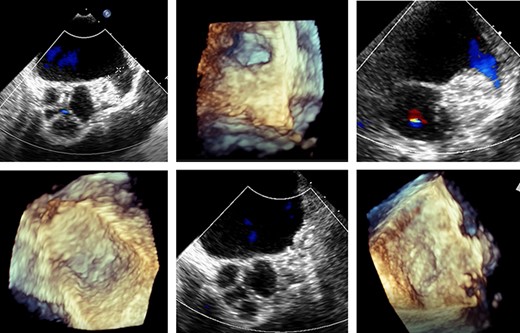

An LAA clip was implanted, under general anaesthesia with a double lumen tube, via a left mini-thoracotomy without a heart-lung machine. Briefly, a 7 cm skin incision was made laterally above the left mamilla (Fig. 4). Preparation of the subcutis and pectoralis muscle in the fourth intercostal space exposed the LAA. The LAA clip (AtriCure 40 mm) was placed over the LAA to its base. Transoesophageal echocardiography was used to complete LAA closure, the clip was closed and holding device removed (Fig. 5). The patient received 2.5 mg fondaparinux once daily to prevent thrombosis formation; once mobile anticoagulation was stopped. Five days post intervention, the patient was discharged in good clinical condition. Wound healing was uneventful at 10 days. After 1 year without anticoagulation, no further complications were observed.

Transoesophageal echocardiography control of the LAA clip in correct position at the LAA base with display of the complete LAA closure.